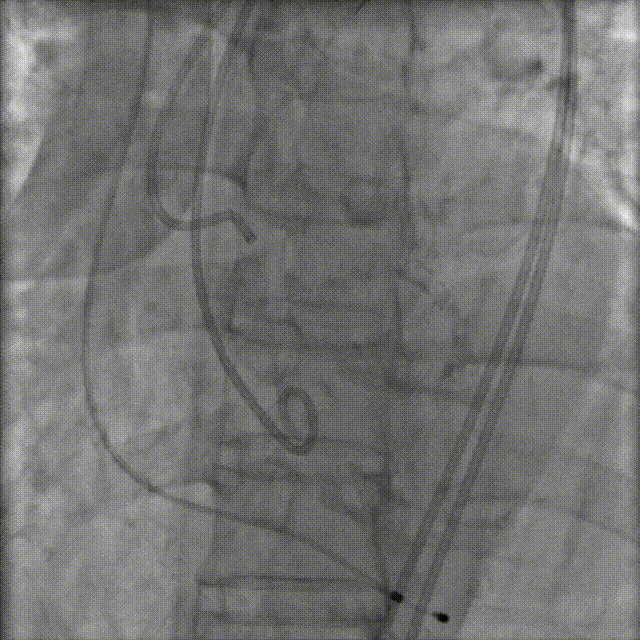

TaurusNXT植入过程

手术采用20mm Z-Med II球囊进行预扩张,植入AV23 TaurusNXT主动脉瓣。在左右重合位影像(cusp overlap view)下释放瓣膜达到工作位,造影显示锚定位置理想,快速释放到回收极限位后在右窦中心位(coplanar view)下再次确认植入位置,同时超声评价瓣膜位置及血流动力学情况,确认无误后精准缓慢释放瓣膜。术后即刻超声心动图评估显示瓣膜位置良好,无瓣周漏,主动脉狭窄及反流均完全解除,主动脉瓣口峰值流速为1.89m/s,平均跨瓣压差为8mmHg,有效瓣口面积为2.01cm²,血流动力学指标理想,未再进行球囊后扩张,整个手术时间仅耗时1小时。